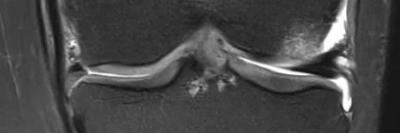

Hautfalte am Knie nach Sportunfall: Was war kaputt?

Ein 48-jähriger männlicher Patient stellt sich nach einem Sportunfall mit Kniegelenksbeteiligung vor. Er war beim Rollschuhhockey mit einem Gegner zusammengestoßen. Er beschreibt starke Schmerzen und ein deutliches Instabilitätsgefühl. Die Haut ist im Bereich des innenseitigen Kniegelenks deutlich eingezogen. Welche Bänder sind gerissen und wie ist es dazu gekommen?

Pincer-Konstellation, Hüftdysplasie und CAM-Impingement im Röntgenbild/© Fehske K / all rights reserved Springer Medizin Verlag GmbH, Sonographiequerschnitt über der Hälfte des M. quadriceps (Normalbefund)/© Gehlen M et al. / all rights reserved Springer Medizin Verlag GmbH, Mediale Meniskusallografttransplantation /© Winkler PW et al. doi.org/10.1007/s43205-025-00320-y unter CC-BY 4.0, Sehnentransplantate zur Rekonstruktion des vorderen Kreuzbands /© Fink C et al. doi.org/10.1007/s00113-025-01551-4 unter CC-BY 4.0, Knie-MRT zeigt überlastungsbedingte Knochenmarködeme/© Brockmeyer M et al. / all rights reserved Springer Medizin Verlag GmbH, Läufer umfasst sein Sprunggelenk/© PeopleImages / Getty Images / iStock (Symbolbild mit Fotomodell), Gruppe beim Rückentraining im Fitnesscenter/© Robert Kneschke / stock.adobe.com (Symbolbild mit Fotomodellen), Walking mit Kniebandage/© Suzi Media Production / Getty Images / iStock (Symbolbild mit Fotomodell), Vordere Kreuzbandruptur/© Springer-Verlag Berlin Heidelberg 2016, Operation zum Kniegelenkersatz/© Issara / stock.adobe.com, Ein kleines Kind hüpft auf einem Trampolin/© anzebizjan / stock.adobe.com (Symbolbild mit Fotomodellen), Anteriore Schulterluxation im Röntgenbild/© Spagna G et al. / all rights reserved Springer Medizin Verlag GmbH, Laufschuh binden/© ssoil322 / stock.adobe.com, Hämatom an der Stirn des 9-Jährigen/© Dr. med. Thomas Hoppen, Innenseitige Hauteinziehung bei eingeschlagenem Innenband/© Akalin ER et al. / all rights reserved Springer Medizin Verlag GmbH, Rekonstruktion der Halswirbelsäule im CT/© Prof. Klaus Schunk, Sonografie am Fußgelenk/© A. Schuh, Gebrochener Fuß im Gips/© Aleksandr Kirillov / stock.adobe.com (Symbolbild mit Fotomodell), Search Icon, Arthropedia, Frau unkenntlich fasst sich ans Knie/© Pornpak Khunatorn / Getty Images / iStock (Symbolbild mit Fotomodell), Ärzteteam führt Hüftoperation durch/© ATRPhoto / stock.adobe.com (Symbolbild mit Fotomodell)